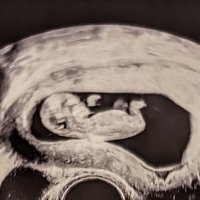

Alt såg bra ut på OTUL 12+3

Vis vedlegget 456172

Lov å tippe kjønn om dere vil/ser noe![]()

Dette er tydelig ei jente!Vis vedlegget 456171